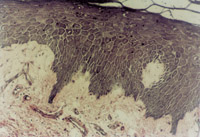

傷后12h急診入院,檢查雙下肢為淺Ⅲ度燒傷。創(chuàng)面表皮已壞死剝脫,真皮層變性壞死呈蠟黃色和蠟白色相間(圖5-3-1)。取局部組織做病理切片檢查,顯示上皮組織全層壞死,真皮層膠原纖維變性,結構紊亂,微循環(huán)瘀滯(圖5-3-2)。

5-3-2 上皮組織全層壞死,膠原纖維變性,微循環(huán)瘀滯 HE×20